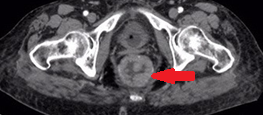

Κόκκινα βέλη. Παχυσμένο τοίχωμα ορθού. Πράσινο βέλος. Περιτονία του μυός ανελκτήρα του πρωκτού (Ευγενική παραχώρηση Dr. V. Penopoulos)